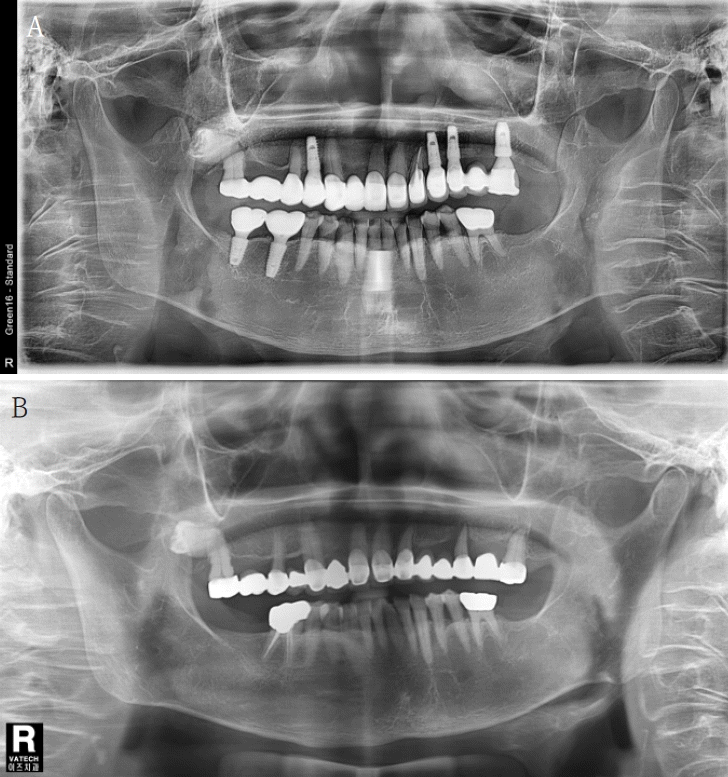

Figure 1.

A. A panoramic radiograph at the last visit. Vertical absorption of alveolar bone around the maxillary second molar on the right side is observed, and bone resorption progressed to the root of the tooth can be confirmed. B. First visit panoramic radiograph (12 years ago). The root of the second molar and the third molar on the right side of the maxilla are close to each other, and the third molar is impacted horizontally.